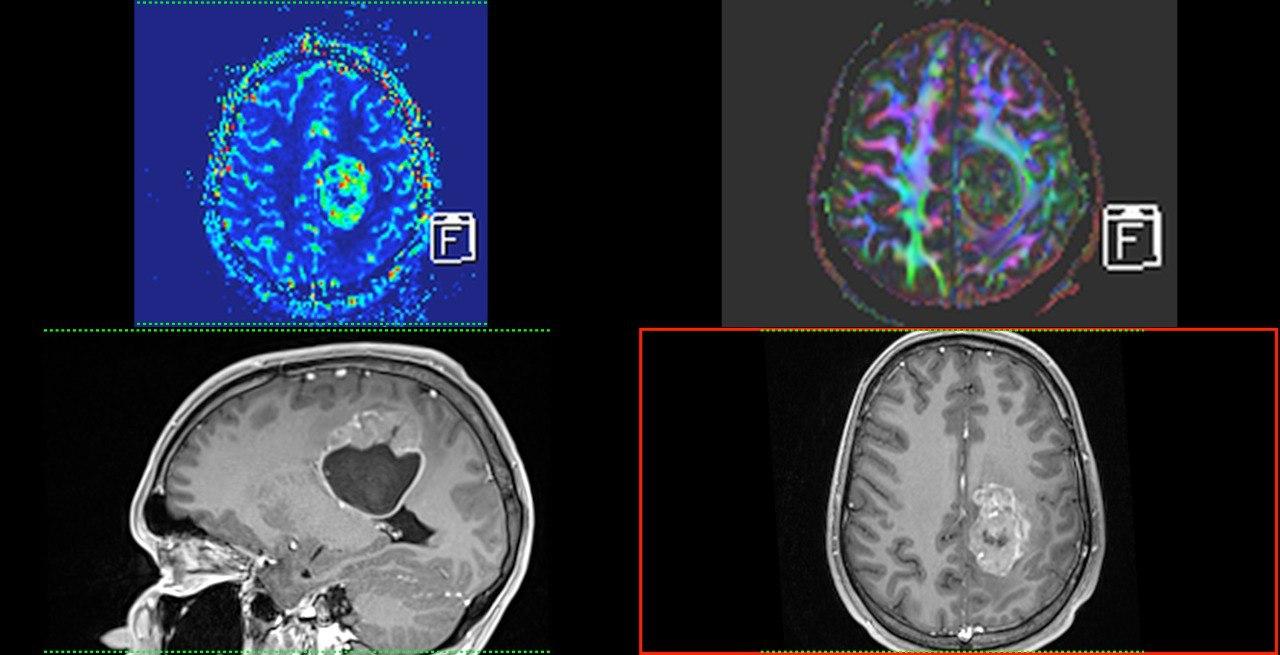

- МРТ: Створює найчіткіші зображення м’яких тканин, органів та судин. Без використання шкідливого випромінювання, тому також підходить для візуалізації вагітних, дослідженні плоду.

У нас є можливість проведення досліджень високої роздільної здатності всіх органів та систем (за винятком серця), зокрема в складі синдромів/комбінованих вадах. Обстеження виконуються, як для дітей так і дорослих пацієнтів, в т.ч. з анестезіологічним забезпеченням (седація, наркоз).

Завдяки передовим технологіям ми маємо можливість проводити МРТ дослідження “всього тіла” (whole body)*, мультипараметричні обстеження головного мозку та простати з наявними програмами МР-трактографії (DTI), МР-спектроскопії, також виконуємо безконтрастну МР-ангіографію інтракраніальних судин, шиї; МР-холангіопанкреатографію, ентерографію, визначення перенавантаження залізом печінки.